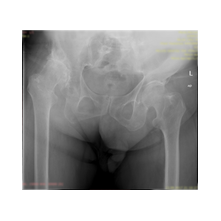

Koksartroz (Kalça eklemi kireçlenmesi), protez cerrahisi ile çözüm bulmaya çalıştığımız diğer bir rahatsızlıktır.

Peki kalça protezi ameliyatın da neler yapıyoruz? Diz protezi ameliyatındaki benzer aşamaları uyguluyoruz. Kalça eklemi dize göre yapısal olarak ve çalışma sistemi olarak farklıdır. Kalça eklemi bir yuva ve onun içinde hareket eden femur başı dediğimiz bir toptan oluşur. Kalça eklemi kireçlenmesinde bu baş ve yuva yüzeyindeki kıkırdakların aşınması sonucu başın yuvarlaklığı kaybolur, sonuçta ağrı ve hareket kısıtlılığı ortaya çıkar. Bu yüzeyleri değiştirirken öncelikle bu başı kesip atıyoruz. Daha sonra yuvayı yine kılavuzlarla oyup uygun büyüklükteki protezi sıkıştırdıktan sonra en az 2 vida ile kemiğe adapte ediyoruz. Daha sonra alt uyluk kemiğini yine kılavuzlar yardımı ile oyduktan sonra kemiğe adapte ediyoruz ve sistemi birleştiriyoruz.

Görüntüleri büyütmek için üzerine tıklayınız.